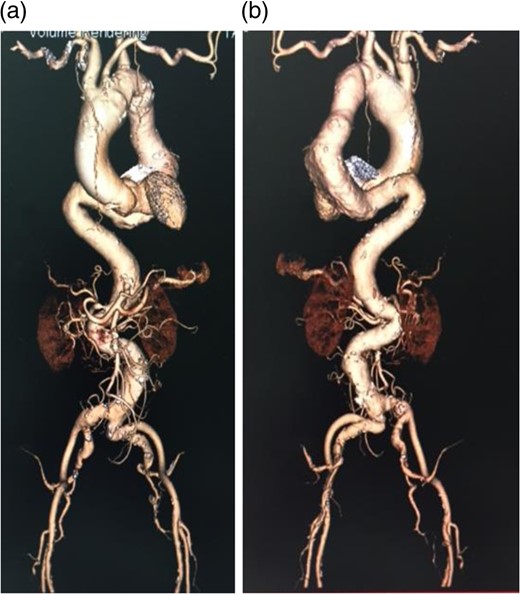

An 80-year-old woman with a past history of cerebral stroke and myocardial infarction was referred to our hospital for treatment of a true fusiform aneurysm (maximum short diameter, 71 mm) in the descending aorta. The preoperative contrast computed tomography (CT) images showed severe angulations in the abdominal aorta and thoracoabdominal aorta below the aneurysm. The most severe angulation was 164° in the thoracoabdominal aorta (Fig. 1). Device delivery was predicted to be challenging.

Preoperative contrast CT 3D image. (a) Anterior view, (b) Posterior view. A severe angulation was observed in the distal site of the thoracic descending aorta. Many angulations were also found in the peripheral vasculature.